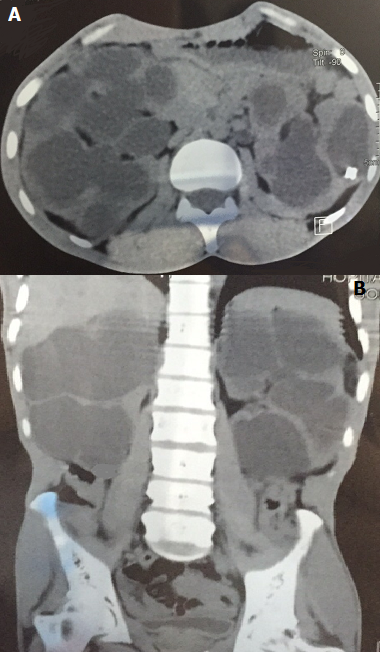

Hydronéphrose géante bilatérale sur syndrome de jonction pyelo-ureterale

Monsieur Z.A âge de 35 ans, sans antécédents particuliers. Il avait consulté pour des douleurs lombaires bilatérales. Cliniquement il était apyrétique, BU négative, l'examen mettait en évidence une volumineuse masse occupant la région lombaire droite. Le bilan biologique avait objectivé une créatininémie à 18 mg/L, et un ECBU stérile. Sur le plan radiologique, l'échographie abdominale mettait en évidencedeux volumineuses masses rénales hydriques et cloisonnées faisant évoquer des reins multikystiques ou une hydronéphrose géante bilatérale. L'Uro scanner retrouvait une hydronéphrose géante bilatérale laminant le parenchyme rénal. Une néphrostomie bilatérale avait été réalisée et avait permis d'évacuer environ 5 litres d'urines stériles. La pyélographie antérograde était en faveur d'un syndrome de jonction bilatéral confirmer par la scintigraphie dynamique. Enfin le patient fut perdu de vue par la suite, quelques mois plus tard il revient avec une insuffisance rénale terminale; Un suivi néphrologique avait été préconisé. Nous présentons cette observation afin de montrer l intérêt du diagnostic précoce et du suivi du syndrome de jonction pyelo ureterale.